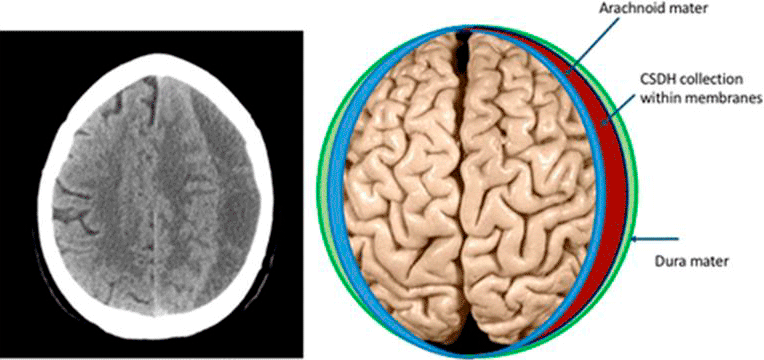

Subdural hematoma is a collection of blood between the skull and the brain. The brain is covered by the meninges, a three layered membrane whose outer layer is the dura mater, the middle layer is the arachnoid mater and the inner layer is the pia mater that covers the brain.

The skull is an unyielding, tight space. If there’s bleeding within this space, pressure builds up, distorting the brain causing life threatening symptoms. In patients with a subdural hematoma, blood accumulates beneath the dura mater.